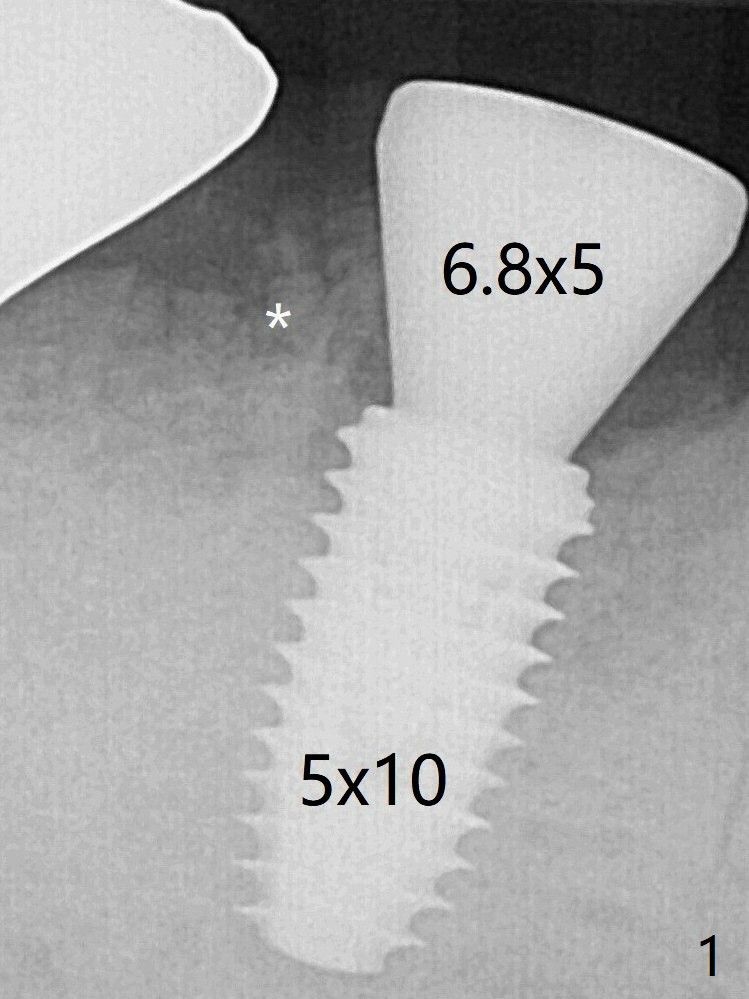

To reduce heat-induced bone necrosis at #19, osteotomy is conducted slowly with copious irrigation with cold saline. Bone density is felt while a 5x10 mm implant is being placed after using cortical tap to the 2nd line of the implant driver. The implant needs to be reverse torqued several times before reaching its final depth (Fig.1 (~50 Ncm)). Since the residual roots are superficially positioned, the immediate implant looks as a delayed one. Although the implant is placed mesial to the septum clinically, its position in X-ray seems to be normal. Because of severe wear and lack of vertical height, a 6.8x5 mm healing abutment is placed. Retention of bone graft placed in the distal socket (Fig.1 *) is maintained by spreading setting acrylic into the edentulous undercut areas. The bone graft placed in the distal socket appears to have been converted to the native bone 3.5 months and 4 months postop (Fig.4,6).